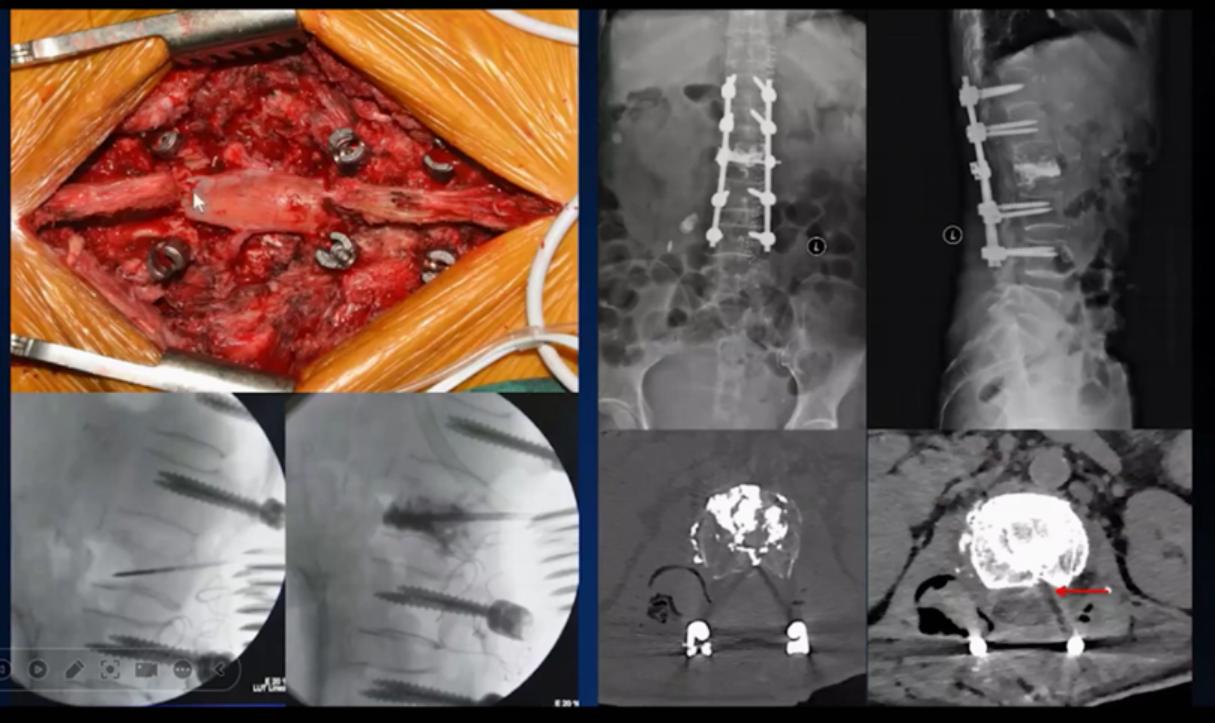

(8)手术实拍图片,胆小勿看!!!

点赞(0) 举报附图资料、仅供参考。